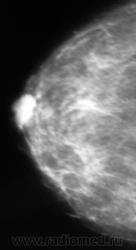

Ещё одна интересная маммография

Кистозный ФАМ с одной стороны просто ФАМ с другой (где право-лево не указано на снимках)

Где прямые, где косые? Вероятно кисты, но могут быть и фиброаденомы, надо УЗИ и при кистах - пункционное удаление содержимого, при фиброаденомах - секторальная резекция.

А, мне, что-то больше симпатично, как "фиброаденомы".

Гадать кисты это или фиброаденомы без УЗИ - дело не благодарное, почему кисты ставлю на первое место потому, что чаще кисты бывают множественными.